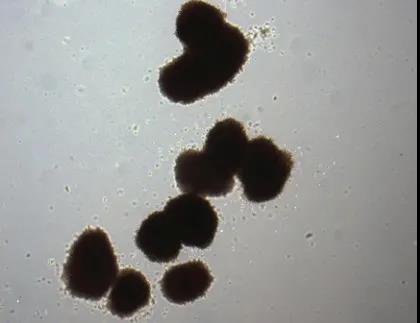

四川大學(xué)華西醫(yī)院探索干細(xì)胞治療糖尿病腎病機(jī)制的最新研究發(fā)現(xiàn),臍帶間充質(zhì)干細(xì)胞可能通過影響SGLT2的表達(dá),發(fā)揮控制血糖和抗炎的效果。